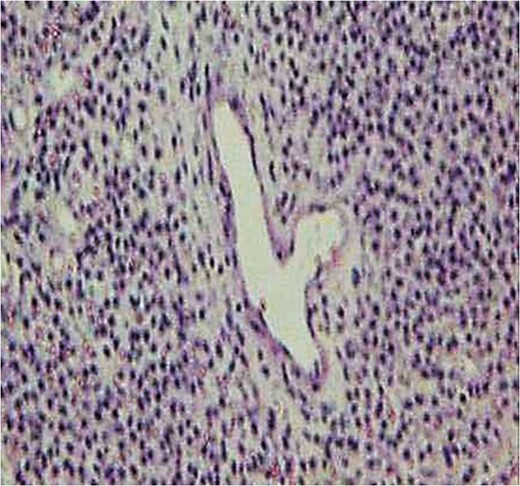

Pathological examination showed that the proliferation of spindle-shaped pericytes had surrounded the ecstatic blood vessels to create a so-called ‘staghorn structure’ (Fig. 4). The vimentin and actin studies were positive, whereas negative results were obtained from studies on CD 34, S-100 protein and cytokeratin.

Pathological section (H-E staining). A proliferation of spindle-shaped pericytes surrounding the ectatic blood vessels to form a so-called ‘staghorn structure’ was shown.